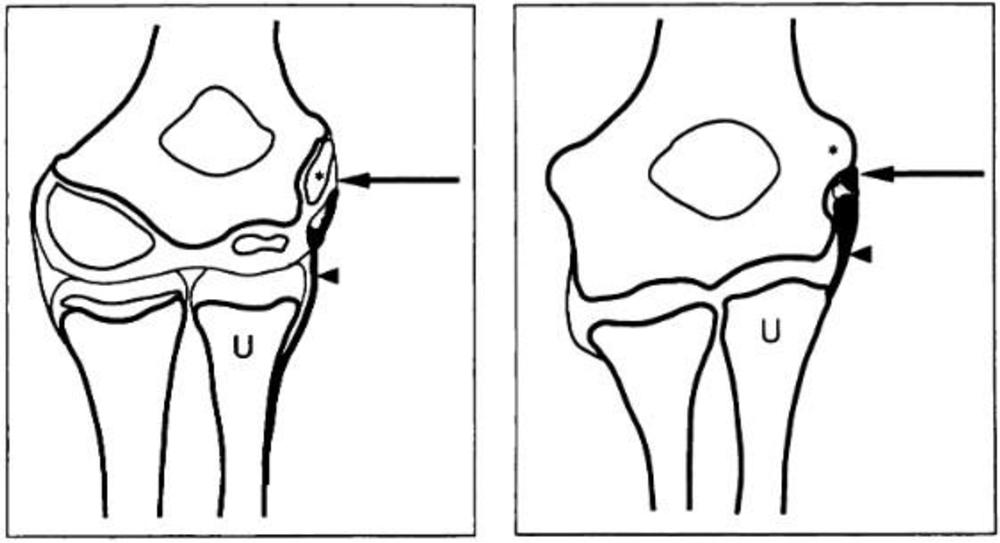

Advanced MRI sequences have revealed that a significant proportion of active elite rugby players experience changes in brain white matter from their participation in the sport, according to research published online July 22 in Brain Communications.

After evaluating 44 adult elite rugby players with diffusion-tensor imaging (DTI) and susceptibility-weighted imaging (SWI), researchers from the U.K. found either axonal injury or diffuse vascular injury in nearly one-fourth of the players, as well as abnormalities of fractional anisotropy and other diffusion measures in nonacutely injured patients. In a subgroup of 18 patients who were followed over time, volumetric MRI showed unexpected mean reductions in white-matter volume.

The researchers used DTI to assess for diffuse axonal injury and SWI to evaluate for diffuse vascular injury. These findings were then compared with control subjects consisting of 15 athletes in noncollision sports and 32 nonathletes.

The investigators found that 10 (23%) of the rugby players had evidence of either axonal injury or diffuse vascular injury. These changes were observed in players with and without a recent head injury.

In the 18 players who participated in longitudinal testing, volumetric structural imaging revealed abnormal mean changes in white-matter volume between the baseline and follow-up MRI scans performed an average of a year later. These changes were not related to self-reported head injury or neuropsychological test scores and might indicate excess neurodegeneration in white-matter tracts affected by injury, according to the researchers.